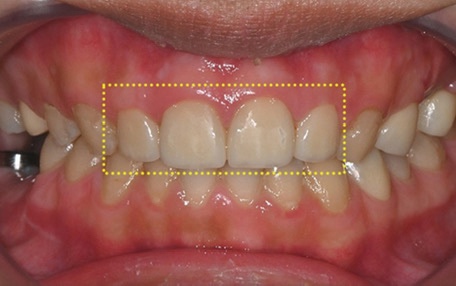

위쪽 어금니 임플란트가 어려운 이유

치아가 빠진 상태로 오래 지내거나

틀니를 장기간 사용한 경우,

또는 나이가 들면서 자연스럽게

잇몸뼈가 점점 흡수되면

임플란트를 심기에 필요한 뼈 높이가

부족해질 수 있습니다.

이 상태에서 임플란트를 바로 진행하면

고정력이 약해질 수 있고,

시간이 지나면서 흔들림이나 불편감으로

이어질 가능성도 커집니다.